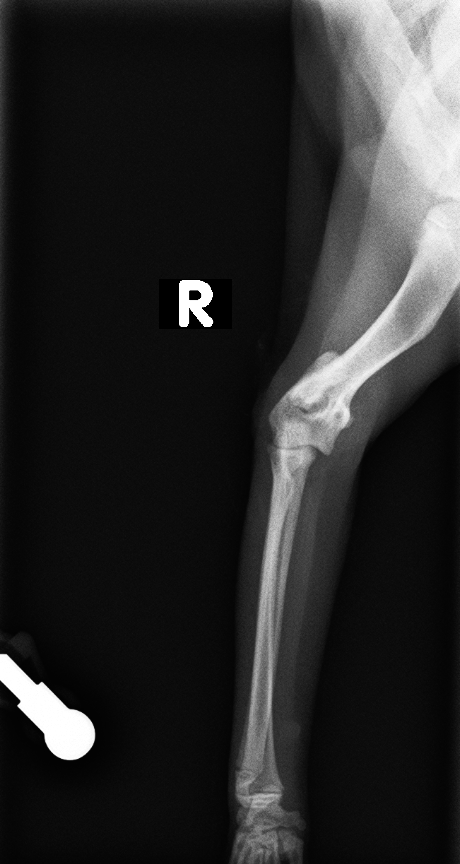

橈尺骨折(海面骨移植)

肘頭骨折

脛骨粗面成長板骨折